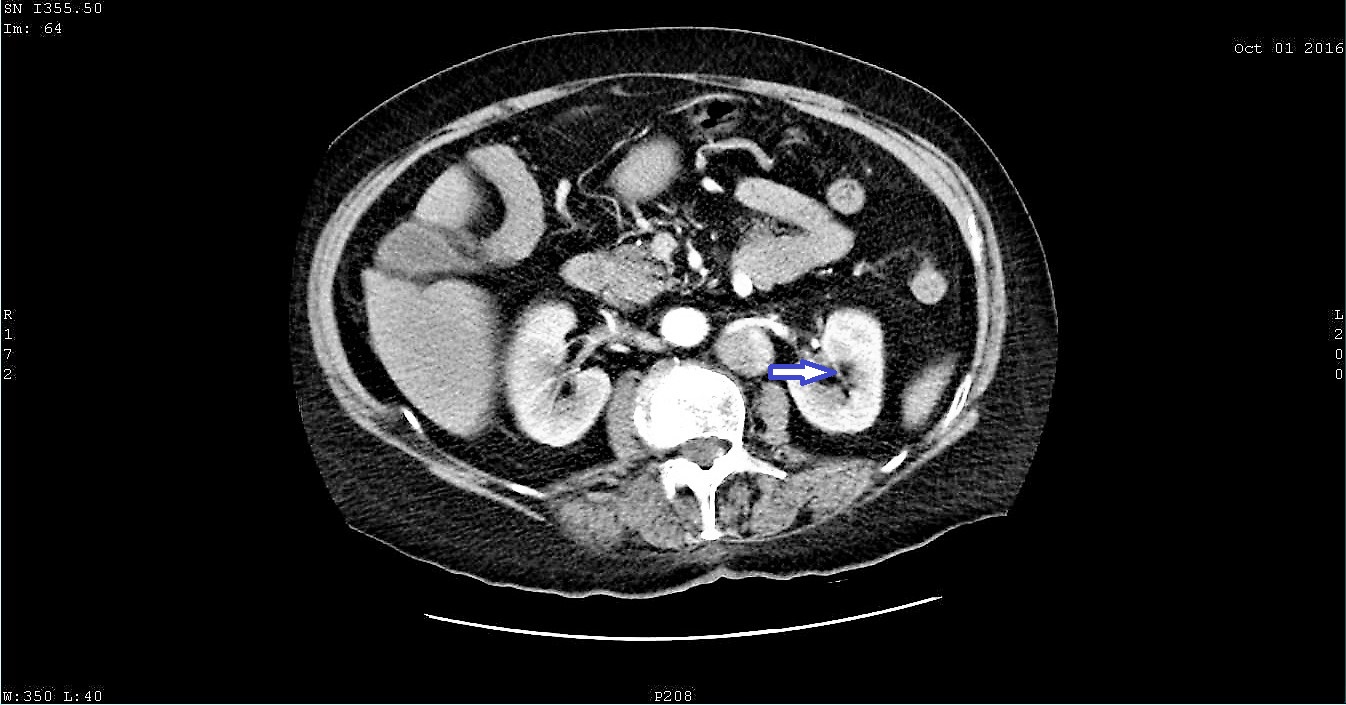

Paradoxical embolism is an uncommon cause of arterial occlusion with a high mortality burden. Current evidence suggests that patent foramen ovale is the most important etiological factor of paradoxical embolism, by acting as a pathway for a thromboembolic material originating from the peripheral veins, passing through the lungs and entering the systemic circulation. Here we present a case of paradoxical embolism in the mesenteric and renal arteries associated with pulmonary embolism and deep vein thrombosis in an elderly woman with no predisposing risk factor. A diagnosis of paradoxical embolism was considered and the presence of a patent foramen ovale was consequently confirmed with a transesophageal echocardiography. Urgent thrombolysis saved the life of the patient. Paradoxical embolism represents an emergency and therefore prompt diagnosis and initiation of therapy may prevent adverse outcomes.